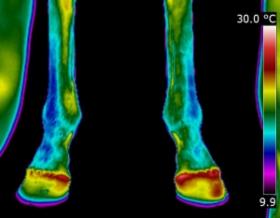

| DISTAL LIMB

| Thermography can point to potential conditions through changes in heat patterns, before the horse shows any clinical signs of injury. It can also reveal hidden signs that other diagnostic tools cannot. It gives us information we didn't know, we didn't know.

| | |  | | | I am very interested in the distal limb and thermography can be used to provide

you and your professional team additional information about conditions such as navicular syndrome,

laminitis, abscesses and corns. Importantly, it can give us information regarding hoof balance and weight-bearing. Hoof balance, often over looked, is a significant influence in the cause of lameness problems not only locally in the foot but throughout the musculature of the body through compensatory issues.